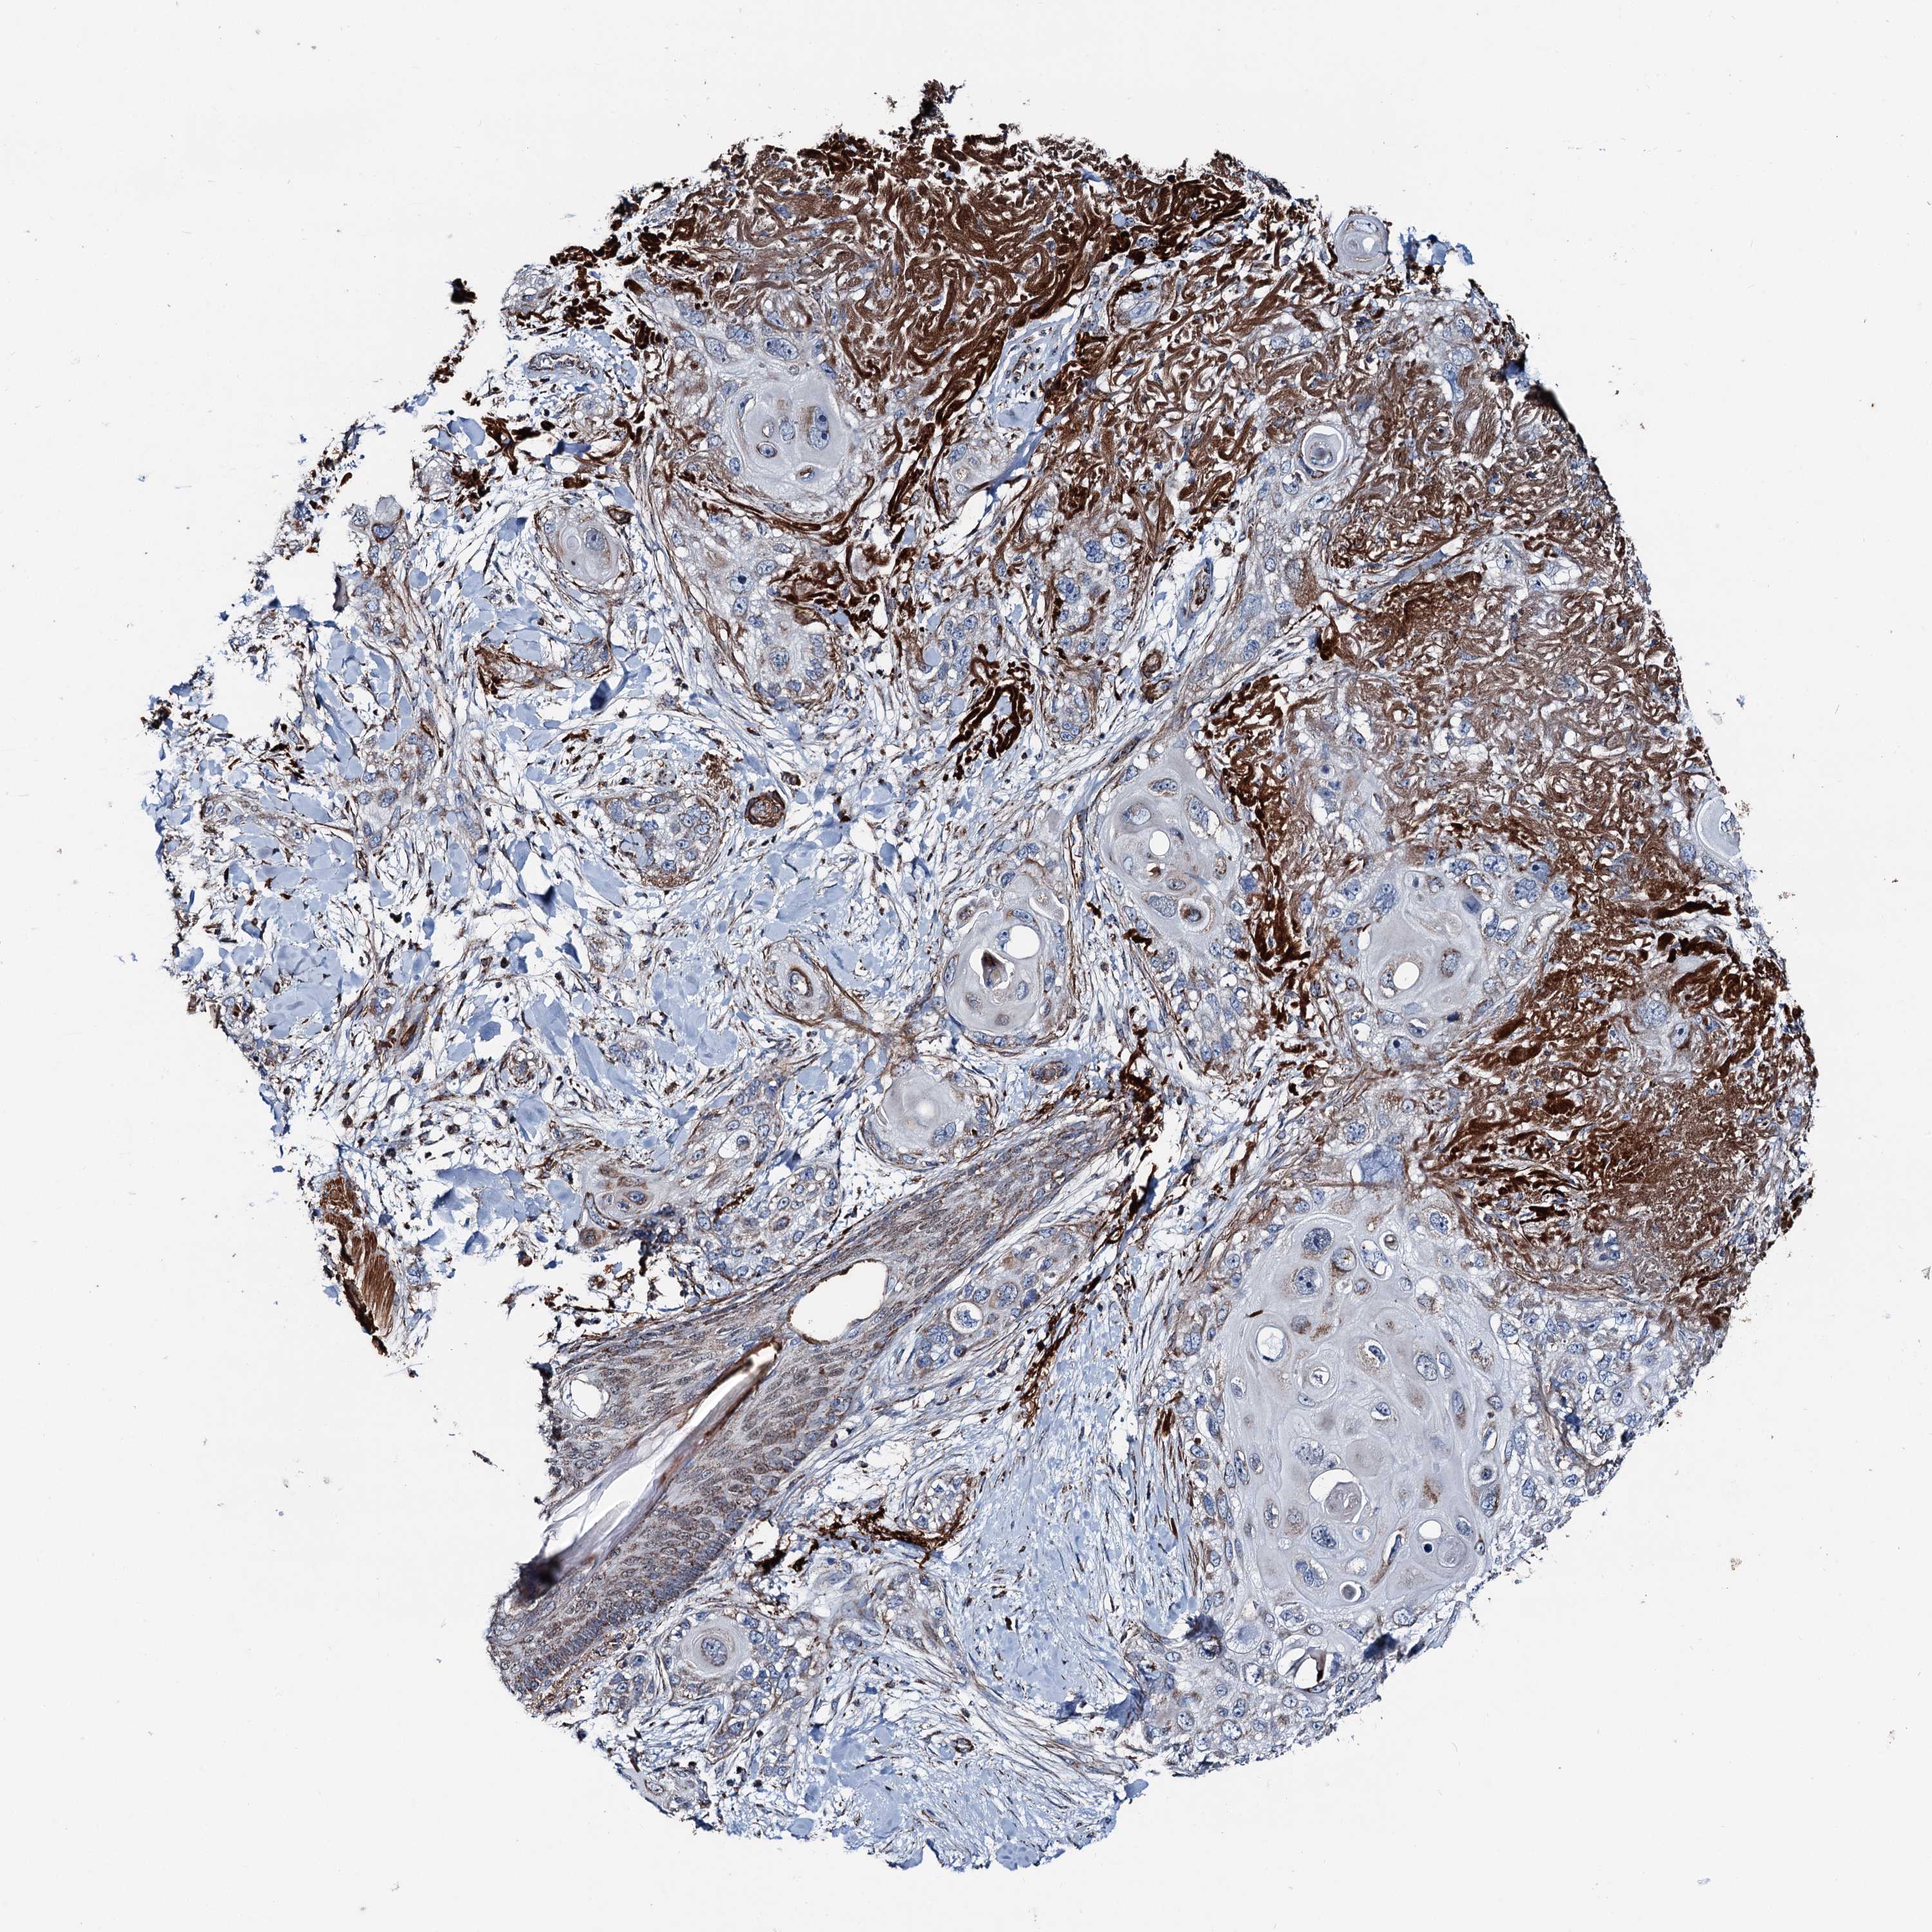

SKIN CANCER - Protein expressioni

A mouse-over function shows sample information and annotation data. Click on an image to view it in a full screen mode. Samples can be filtered based on level of antibody staining by selecting one or several of the following categories: high, medium, low and not detected. The assay and annotation is described here.

Antibody stainingi

Antibody staining in the annotated cell types in the current human tissue is reported as not detected, low, medium, or high, based on conventional immunohistochemistry profiling in selected tissues. This score is based on the combination of the staining intensity and fraction of stained cells.

Each image is clickable and will lead to virtual microscopy that enables deeper exploration of all samples and also displays staining intensity scores, fraction scores and subcellular localization as well as patient and tissue information for each sample.

Antibody HPA038540

Antibody HPA038541

Staining

High

Intensity

Strong

Quantity

>75%

Location

Nuclear

Basal cell carcinoma

Squamous cell carcinoma, NOS

Squamous cell carcinoma, metastatic, NOS